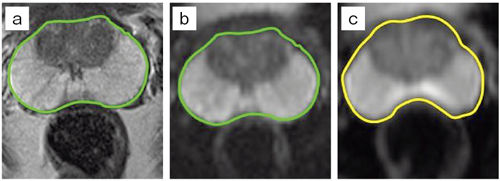

DWIやEPIシーケンスの問題点は,局所の磁化率による信号低下や歪みである。局所励起により,各軸のエンコードが低減できるため,磁化率の影響を受けやすい領域で拡散の定量評価がより一層向上すると考えられており,病変の検出を目的としたT2強調像とのフュージョン精度の向上(図6)や,FOV外からの体動によるアーチファクトの減少,体幹部のADCmap,fractional anisotropy(FA)mapの信頼性の向上(図7a,b),近年期待が高まっている体幹部の非造影パーフュージョン・フラクションのためのintra-voxel incoherent motion(IVIM)の高画質化, fMRIにおけるSNRの向上が期待されている。

図6 前立腺の解剖学的画像

(a)とsyngo ZOOMitによる歪みのない画像(b)との輪郭がよく一致している。一方,従来のDWI(c)では前立腺がんの主な好発部位である辺縁域で特に歪みが見られる。